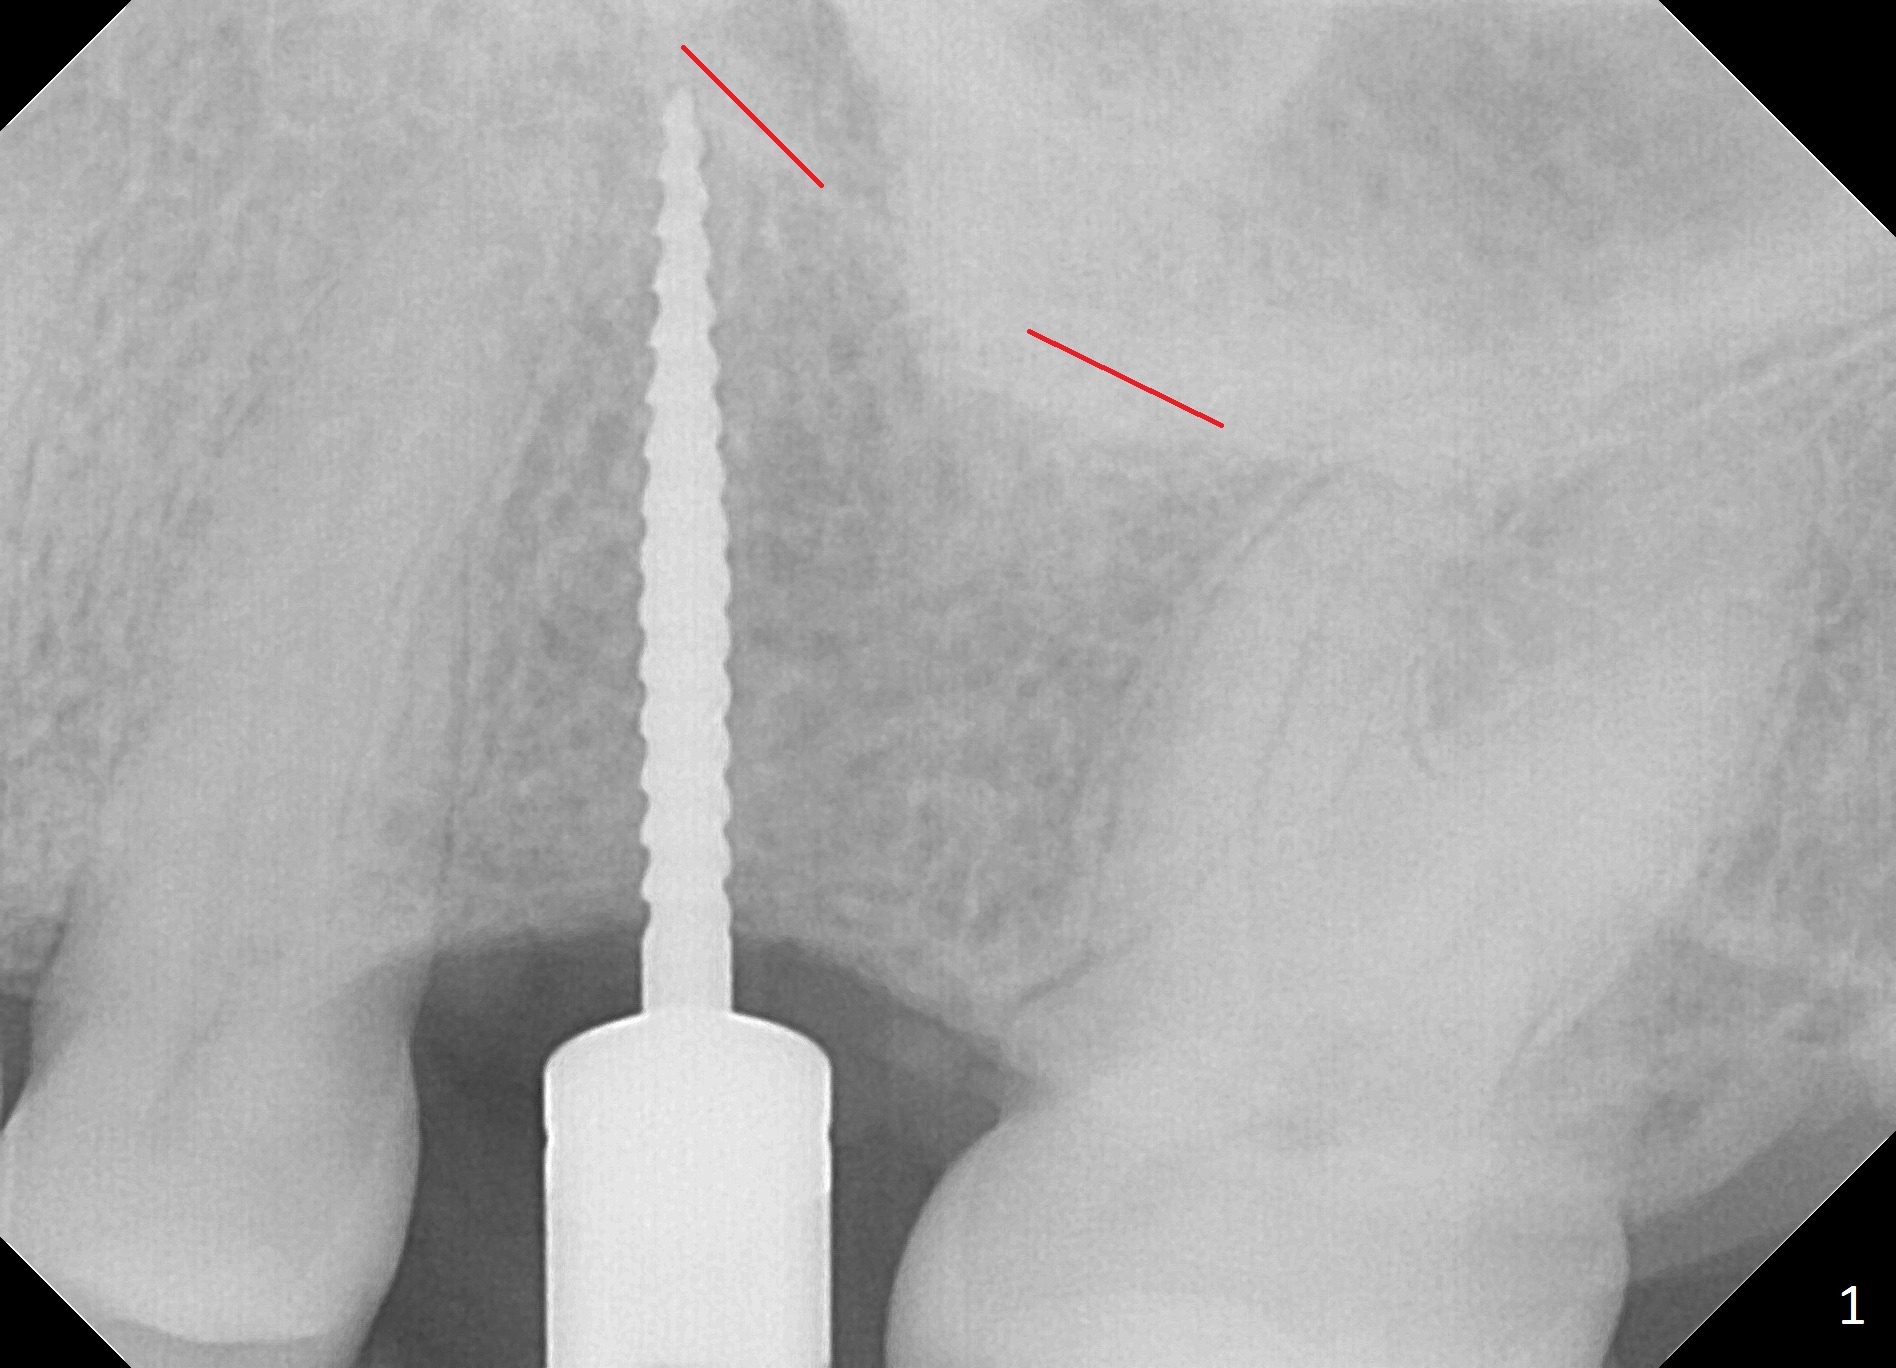

Osteotomy Using Expanders with Drill

The edentulous area at #14 is moderately atrophic, After incision, the bone is too hard for #15 blade for bone expansion. Osteotomy is initiated with 1.2 mm drill, followed by insertion 1.3/2.3 mm bone expander (Fig.1). Use the same instruments are reused twice to change the trajectory (Fig.2,3). Finally Lindamann bur is utilized to move the osteotomy distally by ~ 2 mm; bone expansion continues until 2.4/3.7 mm expander for 13 mm with 50 Ncm (Fig.4). The last expander 3/4.4 mm barely enters the osteotomy for 6 mm. A 3.7 mm drill has to be used for 12 mm before placement of a 4.5x11.5 mm implant with >35 Ncm (Fig.5). A 5.5x5(3) mm abutment is placed with allograft (<) placed around the implant. Following suturing, periodontal dressing is applied around the implant. The abutment dislodges 3 months postop (Fig.6). Crown is delivered 3 weeks later. The abutment screw is retightened ~ 2 months later. He is a bruxer. The abutment screw is loose again <2 years post cementation (6 months post #18 screw retightenting and occlusal reduction), probably related to distal implant placement (Fig.7).